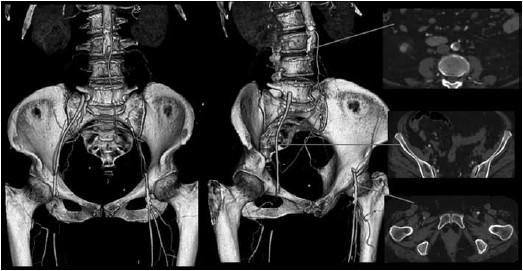

A paciente da questão anterior é submetida a uma angiotomografia de Aorta e ilíacas, sendo a reconstrução arterial 3D e cortes axiais selecionados apresentados a seguir.

Diante do quadro clínico e achado do exame de imagem, assinale a alternativa que corresponde respectivamente à principal hipótese diagnóstica e à conduta terapêutica.

Uma paciente de 65 anos, tabagista 35 anos/maço, obesa e portadora de hipertensão arterial sistêmica é admitida no Pronto Atendimento por queixa de dor de início súbito em membros inferiores, associada a impotência funcional dos membros e queda da própria altura. Seu exame físico demonstra ausência de pulsos desde a artéria femoral, associado a gradiente térmico dos pés. Há parestesia de artelhos e déficit motor à dorsiflexão dos pés. Ademais, ao Doppler de ondas contínuas não há fluxo arterial nas artérias podálicas.